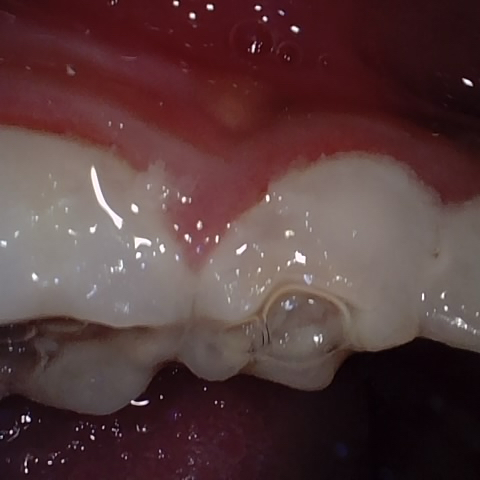

NHD25463

Annotated as "Good"